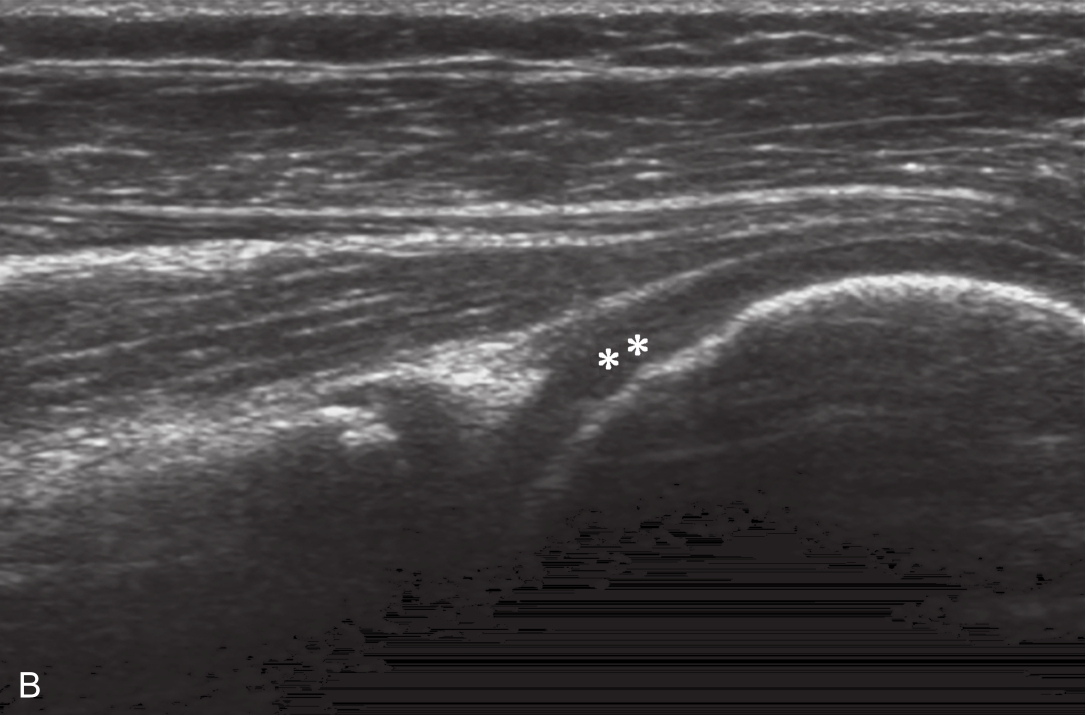

▲ 图2-6-3 超声引导下肩关节腔介入治疗超声图(一)

A、B.二维超声显示肩关节腔少量积液,滑膜增厚;C.超声引导针尖进入关节腔;D.超声示意图,虚线蓝色区域:后关节腔;单星号:腋下关节囊;双星号:后关节腔;短箭头:穿刺针;长箭头:穿刺针路径;L:盂唇;HH:肱骨头